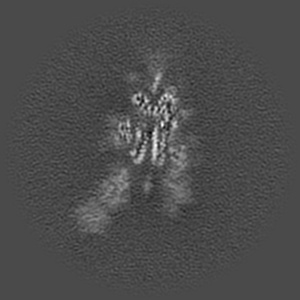

Structure of the SARS-CoV-2 S 6P trimer in complex with the human neutralizing antibody Fab fragment, BG1-24

Sample: Ternary complex of BG1-24 Fab bound to SARS-CoV-2 spike trimer